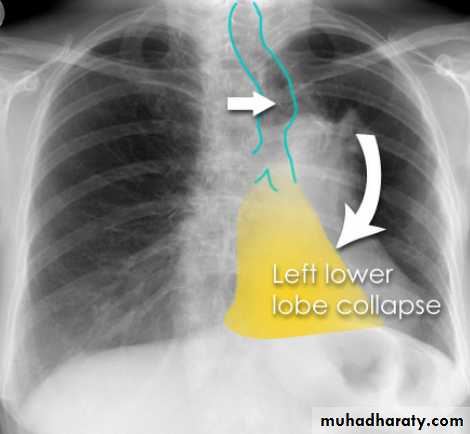

Left lower lobe collapse has distinctive features, and can be readily identified on frontal chest radiographs, provided attention is paid to the normal cardiomediastinal contours. The shadow cast by the heart does however make it harder to see than the right lower lobe collapse

Radiographic features

Left lower lobe collapseis readily identified in a well penetrated film of a patient with normal sized heart, but can be challenging in the typical patient with collapse, namely unwell patients, with portable (AP) often under-penetrated films, often with concomitant cardiomegaly. Features to be observed include :

triangular opacity in the posteromedial aspect of the left lung

edge of collapsed lung may create a 'double cardiac contour'

left hilum will be depressed

loss of the normal left hemidaphgragmatic outline

loss of the outline of the descending aorta

Non-specific signs indicating left sided atelectasis are usually also be present including:

elevation of the hemidiaphragm

crowding of the left sided ribs

shift of the mediastinum to the left

On lateral projection the left hemidiaphragmatic outline is lost posteriorly and the lower thoracic vertebrae appear denser than normal (they are usually more radiolucent than the upper vertebrae) .